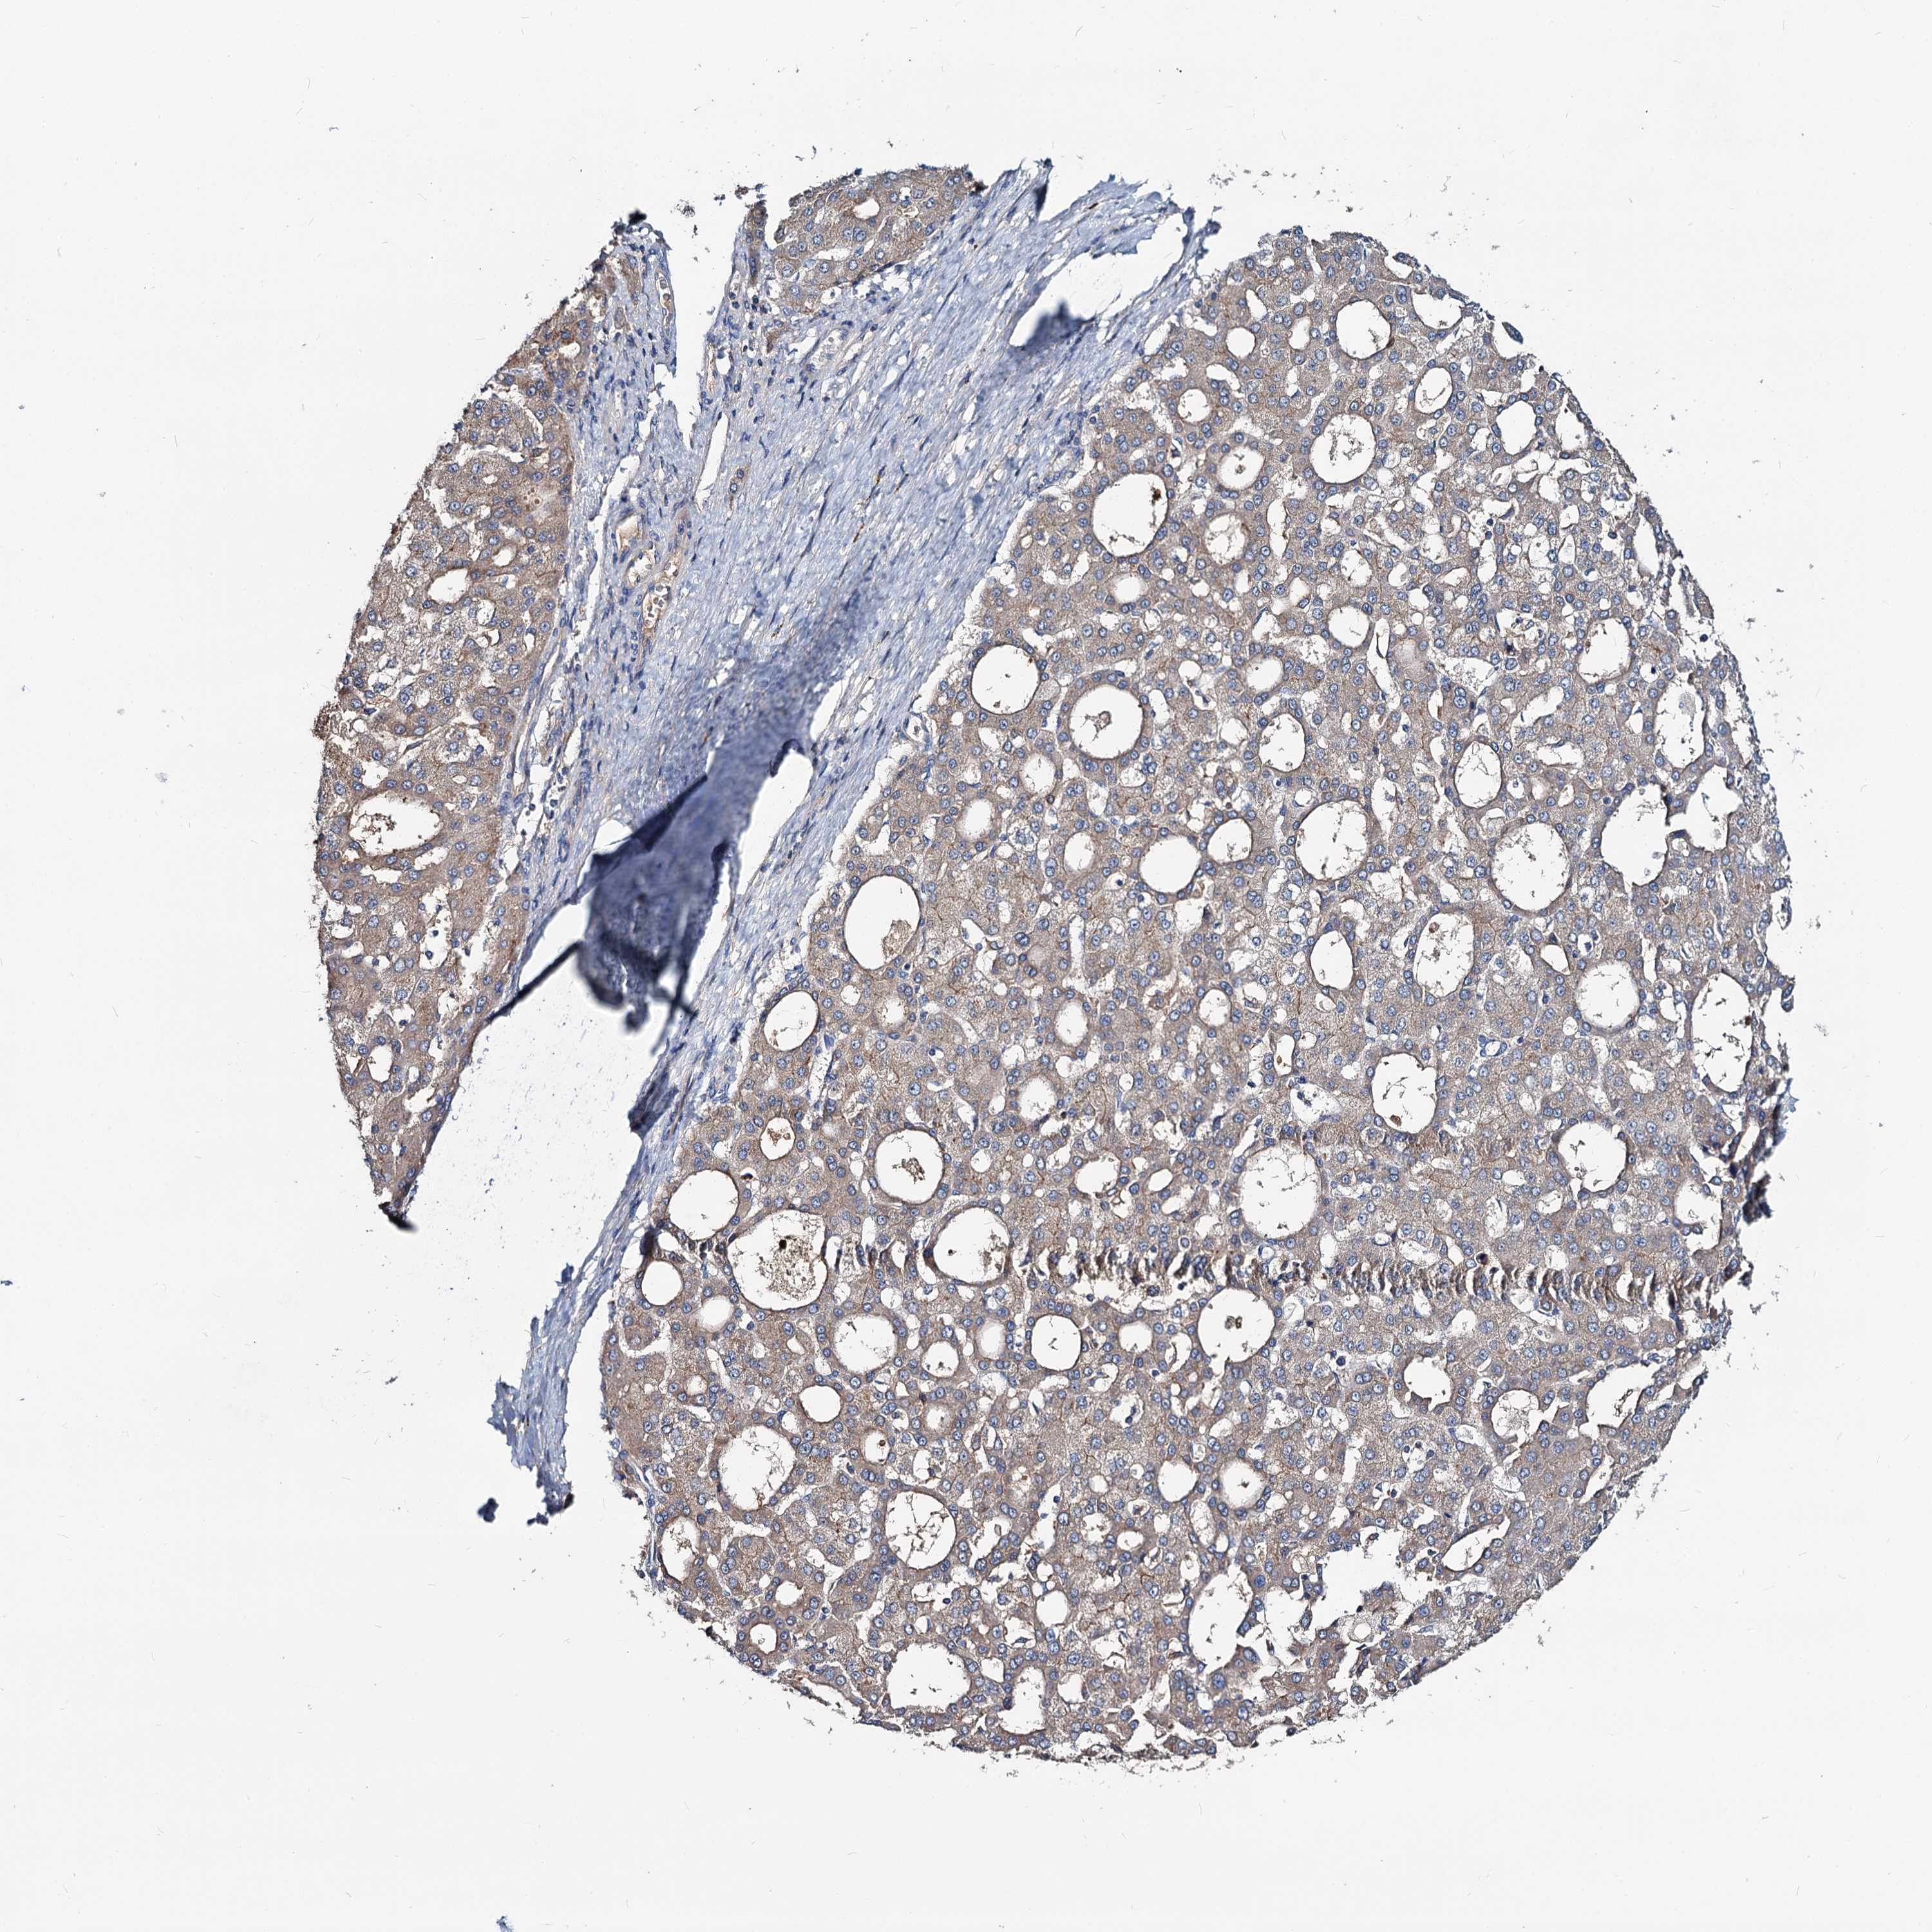

LIVER CANCER - Protein expressioni

A mouse-over function shows sample information and annotation data. Click on an image to view it in a full screen mode. Samples can be filtered based on level of antibody staining by selecting one or several of the following categories: high, medium, low and not detected. The assay and annotation is described here.

Note that samples used for immunohistochemistry by the Human Protein Atlas do not correspond to samples in the TCGA dataset.

Antibody stainingi

Antibody staining in the annotated cell types in the current human tissue is reported as not detected, low, medium, or high, based on conventional immunohistochemistry profiling in selected tissues. This score is based on the combination of the staining intensity and fraction of stained cells.

Each image is clickable and will lead to virtual microscopy that enables deeper exploration of all samples and also displays staining intensity scores, fraction scores and subcellular localization as well as patient and tissue information for each sample.

Antibody HPA039219

Antibody HPA048187

Staining

High

Medium

Low

Not detected

Intensity

Strong

Moderate

Weak

Negative

Quantity

>75%

75%-25%

<25%

None

Location

Nuclear

Cytoplasmic/membranous

Cytoplasmic/membranous,nuclear

Cholangiocarcinoma

Carcinoma, Hepatocellular, NOS